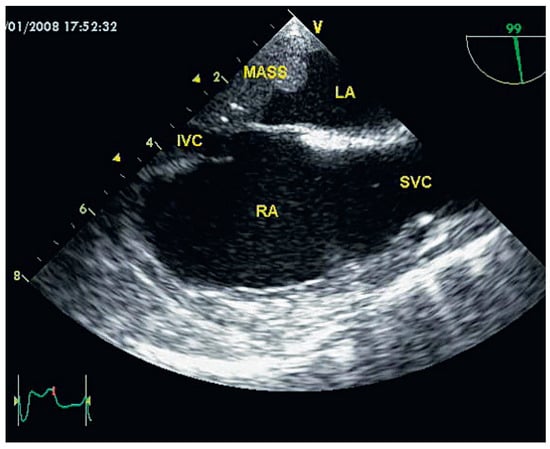

Clinical status showed: BP 150/65 mm Hg. Pulse regular at 82 beats per minute. Peripheral oedema was absent. Several peripheralsigns of aortic regurgitation were noted and a 3/6 protodiastolic murmur was present. Aortic valve replacement was decided and pre-intervention investigations were planed. Transthoracic echocardiography confirmed the aortic regurgitation grade III with mild dilatation of the left ventricle. Thoracic CT scan showed a 30 mm mass located within the left posterior wall (Figure 1). Transoesophageal echocardiography confirmed the location and dimensions of the tumour (Figure 2) and showed in addition involvement of the left atrial wall. Resection of the mass was performed during valve replacement (Figure 3). A 3 cm friable mass attached to the posterior wall of the atrium was easily removed. Reparation of the atrium was performed and a 23 mm aortic artificial valve was implanted. The outcome was uneventful. Histological and immunohistochemical examination conclude to a benign tumorous process compatible with the diagnosis of glomangiopericytoma (myopericytoma) (Figure 4). This was an unexpected diagnosis since to our knowledge it is the first case of cardiac benign haemangiopericytoma reported and secondly because of the patient’s history. A post irradiation tumour would have been more probable. Haemangiopericytoma is a rare tumour. The few one located in the heart were malignant.

Figure 2.

Transoesophageal echocardiography. This view shows the relation between the mass, the left atrium and the inferior vena cava.